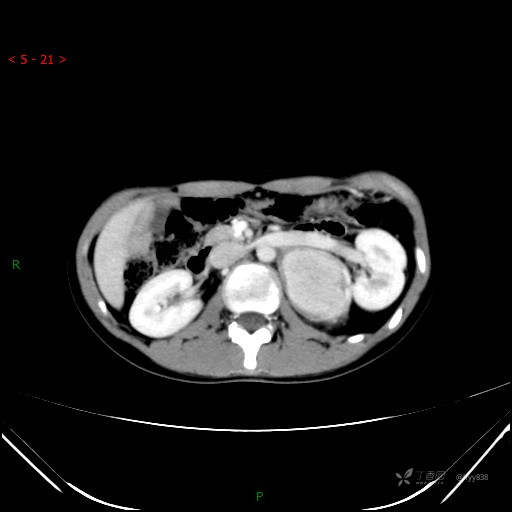

CT值